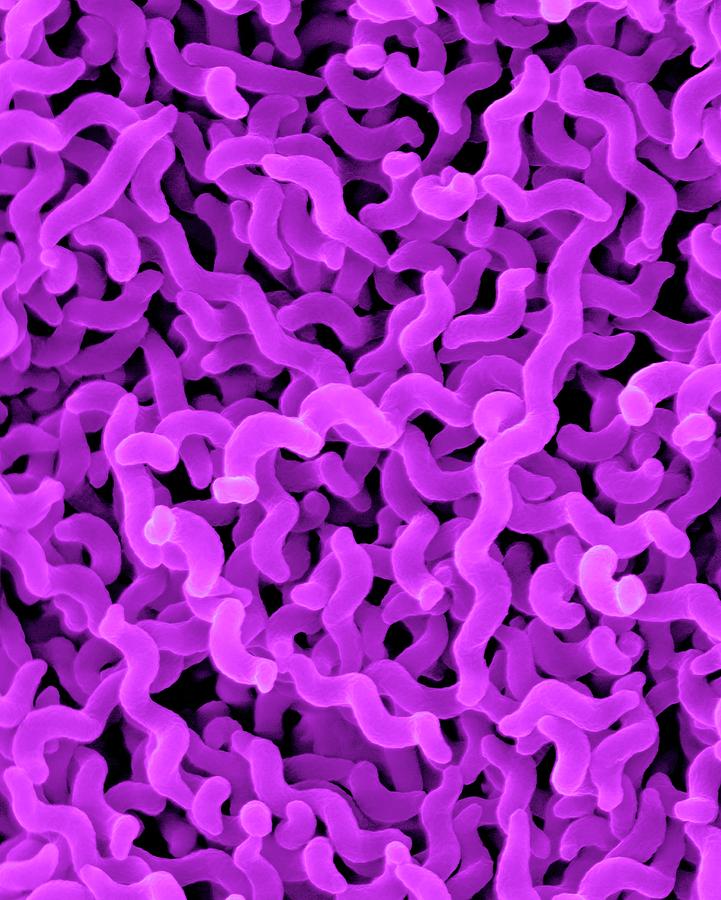

Кампилобактер фетус: патогенез и инфекции